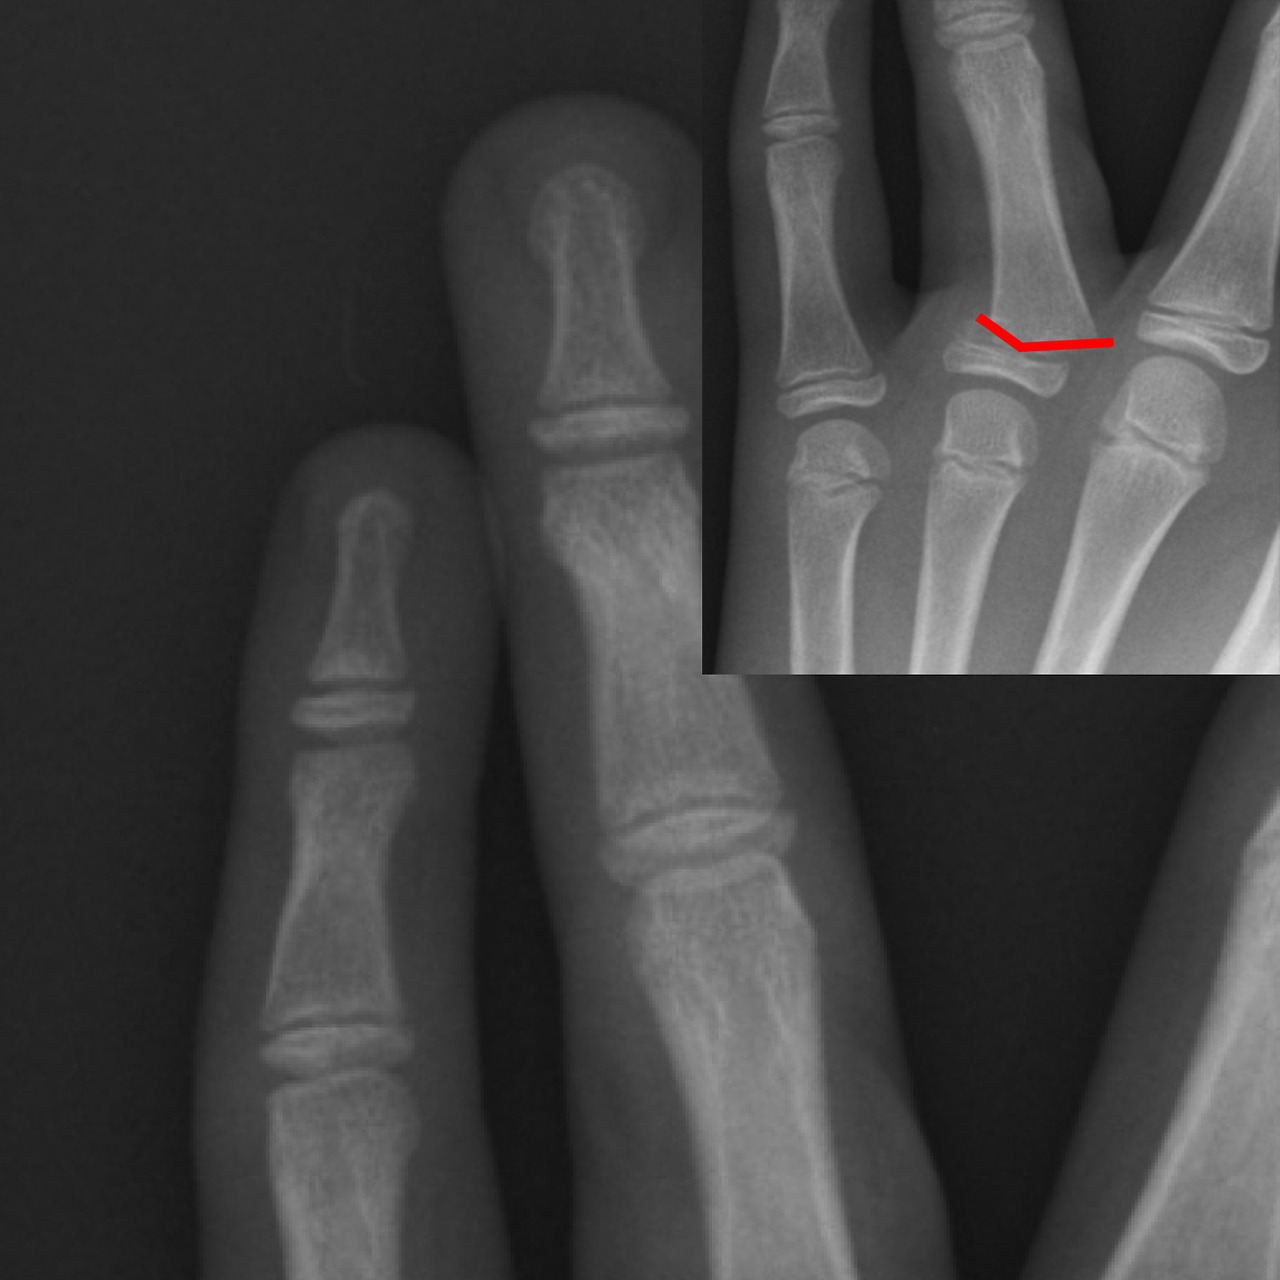

반대로 깁스 또는 보다 강한 고정이 필요한 경우는 다음과 같습니다.

- 골절로 인해 뼈가 어긋난 경우

- 관절면이 손상된 경우

- 여러 조각으로 부러진 분쇄 골절

- 스플린트 착용 후에도 통증과 불안정성이 지속되는 경우